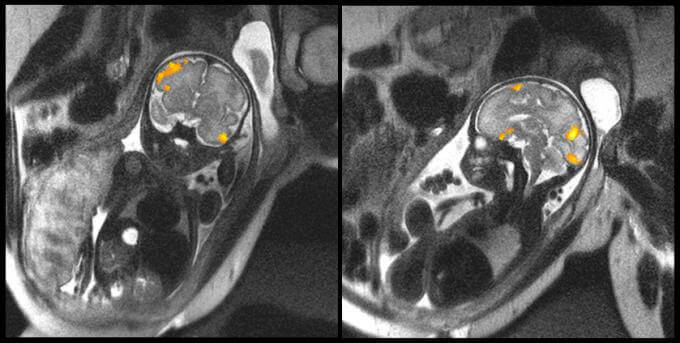

Auf dem oberen Bild können wir die Magnetresonanztomographie eines Fötus in der 20. und eines anderen in der 40. Schwangerschaftswoche sehen. Diese Aufnahmen stammen von der Medizinischen Fakultät der Staatlichen Universität von Wayne (Michigan, USA). Auf ihnen können wir ganz klar die Gehirnaktivität dieser zwei Babys im Mutterleib erkennen.

Mit dieser Untersuchungsmethode wollten die Wissenschaftler vor allem studieren, wie sich die Neuronen der Föten im Laufe der letzten Schwangerschaftswochen verbinden. Die erhaltenen Daten haben Aufschluss über gewisse Aspekte in Bezug auf Frühchen gegeben, die bis zu diesem Moment unbekannt waren.